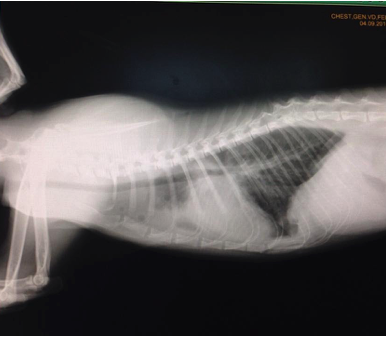

เมื่อตรวจร่างกายจะพบว่า แมวอาจมีน้ำในช่องอกหรือช่องท้อง มีเสียงหัวใจที่ผิดปกติ การเอกซเรย์ช่องอกจะทำให้เห็นเงาของขนาดของหัวใจที่ผิดปกติไป ร่วมกับการตรวจคลื่นไฟฟ้าหัวใจ และยืนยันโรคด้วยการตรวจอัลตราซาวด์หัวใจจะพบการขยายขนาดของหัวใจห้องบนซ้าย และพบการหนาตัวของกล้ามเนื้อหัวใจห้องล่างซ้าย